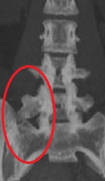

Un mega apófisis transversa es un crecimiento anómalo de la apófisis transversa más caudal de la zona lumbar (la vertebra lumbar más cercana al sacro). Al aumentar de tamaño puede llegar a chocar con el sacro o el íleon produciendo una sobrecarga de la articulación sacroilíaca y producir dolor.Se estima que el 4-8% de las personas tienen una mega apófisis transversa, la aparición de los síntomas se sitúa entre los 30-40 años. El síndrome de Bertolotti es más frecuente en varones y aunque no se sabe por qué es más habitual en el lado izquierdo.

Clasificación.Existen criterios radiológicos descritos por Castelvi que nos permiten clasificar los distintos tipos de mega apófisis transversa.

Tipo I. Apófisis transversa superior a 19mm

Tipo II Lumbarización o sacralización de una vértebra asociado a una diartrodesis entre la apófisis transversa y el sacro (una diartrodesis es una articulación entre dos huesos).

Tipo III La apófisis transversaesta fusionada con el sacro

Tipo IV. Existe una mega apófisis transversa tipo II en un lado y tipo III en el otro.

A su vez los tipos se subdividen en a y b según sea unilateral o bilateral.

La manera más fácil de llegar al diagnóstico de una mega apófisis transversa es con una radiografía simple, de este modo podremos observar el tamaño de la apófisis. El TAC y LA RMN son pruebas que nos ayudan a valorar con más precisión la relación entre la apófisis transversa y el sacro. Para confirmar el diagnóstico muchas veces es necesario bloquear la zona con un anestésico local y ver si disminuye el dolor, en muchas ocasiones puede coexistir un síndrome de Bertolotti con otras causas de dolor lumbar.